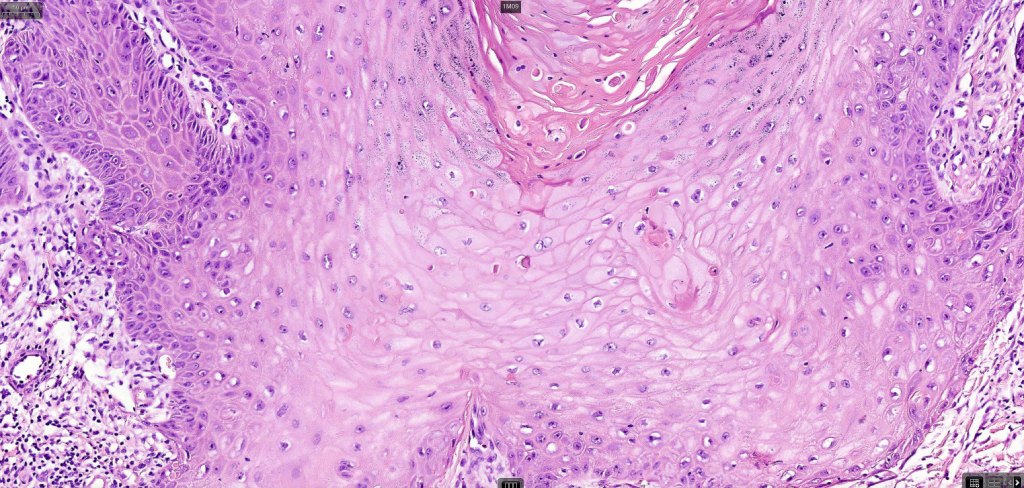

•Well differentiated squamous epithelium often with a characteristic ground-glass appearance

•Only mild pleomorphism & basally located mitoses

•Morphologically like cutaneous lesions with ground glass cytoplasm and very conspicuous dyskeratosis

•Basal mitoses & mild cytological atypia

Below is a fascinating case shared on McKee Derm by Dr. James Simpson. There is an obvious keratoacanthoma but at the edge of the lesion there is marked atypia with nuclear enlargement and pleomorphism. This is also evident in the adjacent epidermis and in the deeper nests.